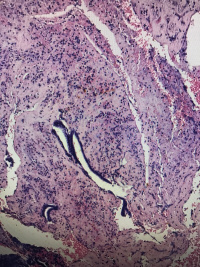

子宫内膜

性别

女

年龄

32

异常流血4天

碎组织一堆,大小2.5✖️2.0✖️0.5cm

少许破碎的增生期子宫内膜

经期内膜。